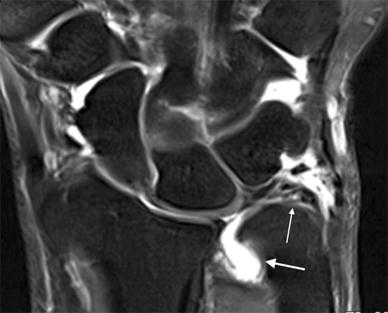

38+ Tfcc Tear Mri Arthrogram Background. The lower circle is of the triangular fibrocartilage complex. Therefore, the mri was normal.

Iv contrast is virtually never indicated in hip joint imaging unless as an indirect mr arthrography technique (see shoulder in. The lower circle is of the triangular fibrocartilage complex. However for scapholunate ligament tears it only had 91% sensitivity and 88% specificity.